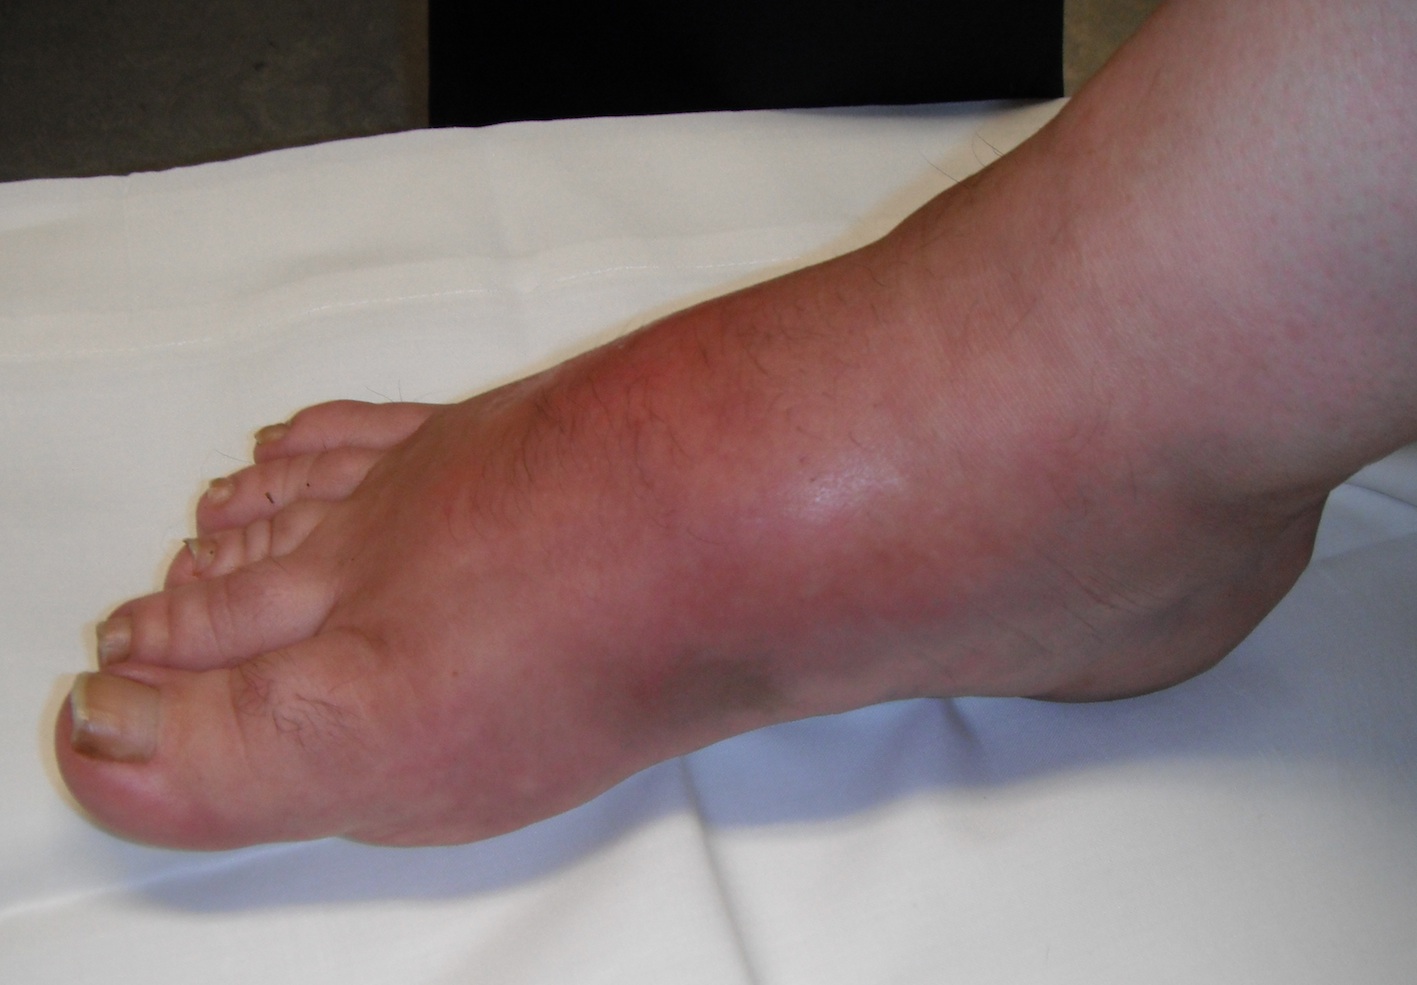

Acute inflammation - swollen, red, warm - reduces with elevation |

Stage 0 / Stage 1

Foot very red

- ? cellulitis

- elevate for 10 minutes and the redness reduces

Reduction of redness with elevation